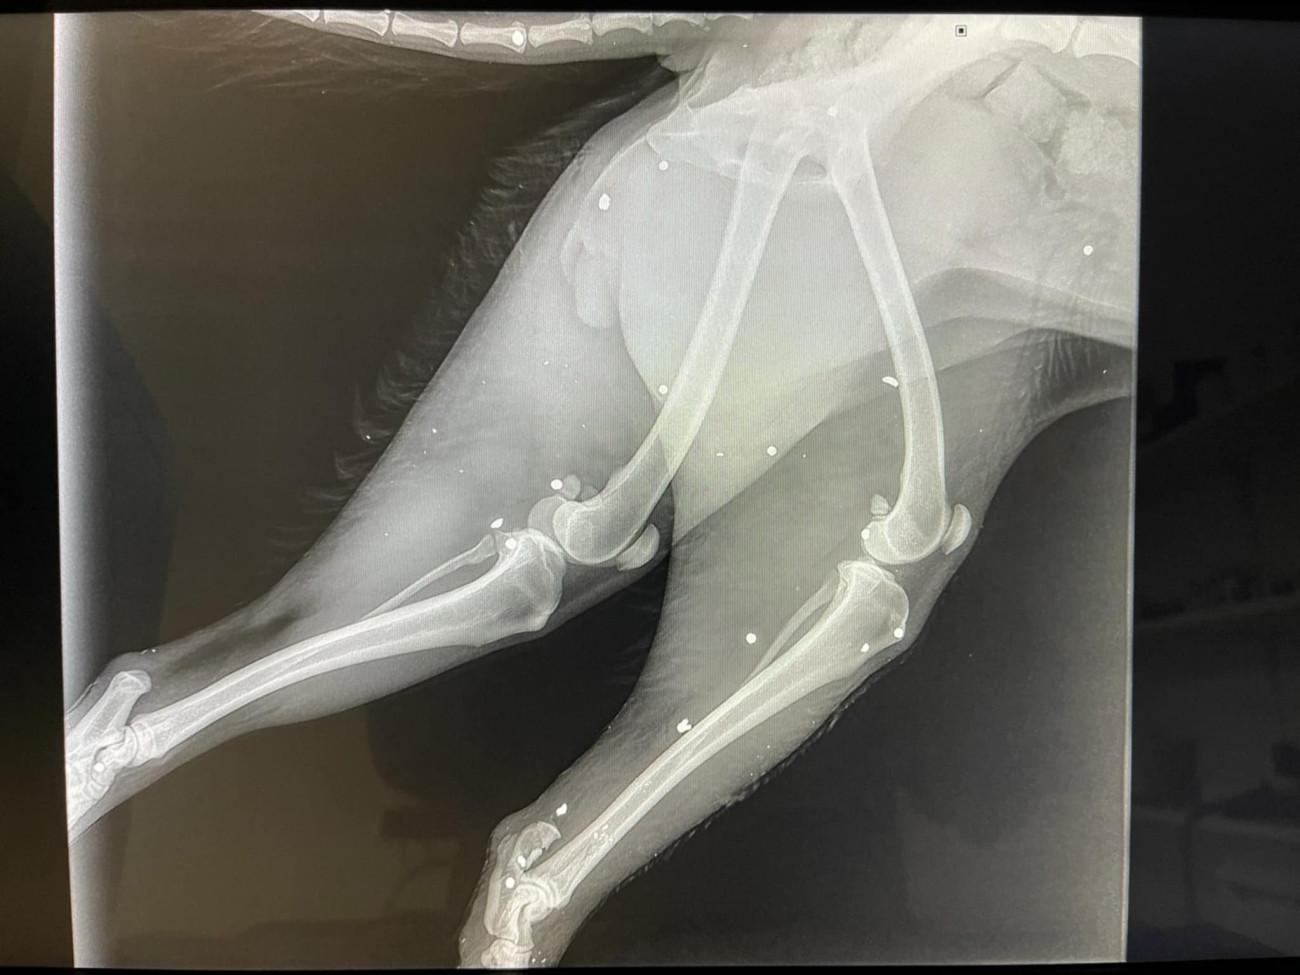

Ακτινογραφία από το σκυλί που δέχθηκε την άγρια επίθεση

Ακτινογραφία από το σκυλί που δέχθηκε την άγρια επίθεση